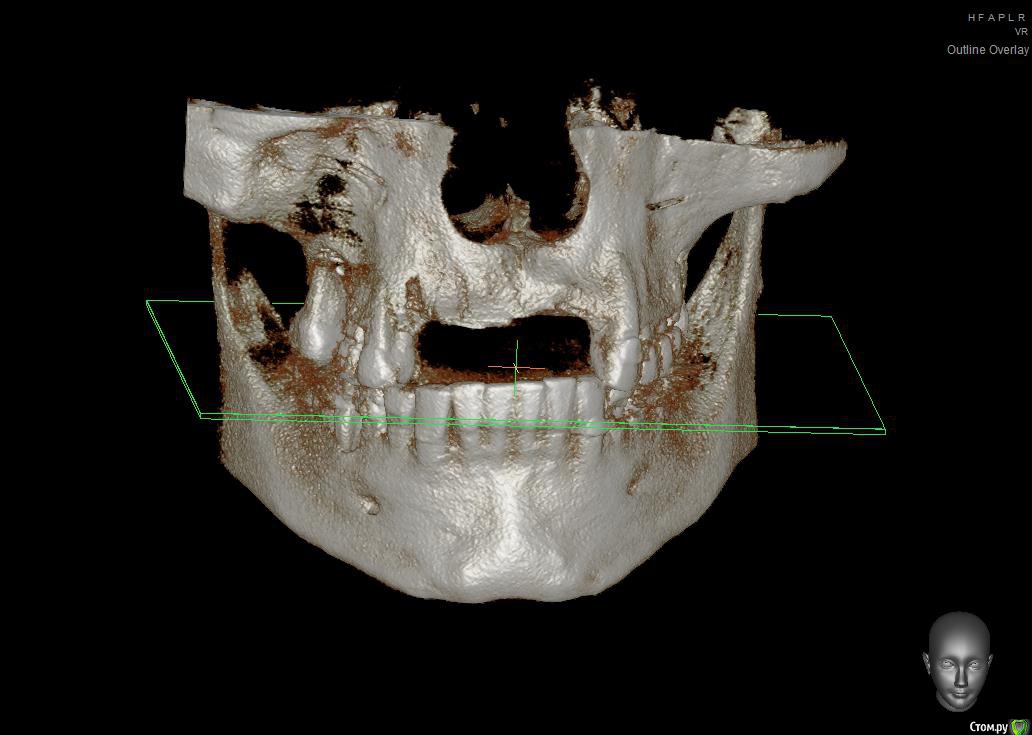

Собственно ситуация такая. Фронтальные зубы сверху были потеряны в результате серьезной травмы,  ! Фактически полное отсутствие костной ткани в области фронтальных зубов и по толщине и по высоте. Пациент ходит с чс протезом и хочет нечто несъемное.

Интересует как лучше это сделать при таких объемных дефектах.  Мои мысли первым этапом сосидж, потом 4 импланта. Но как быть с временным протезированием?